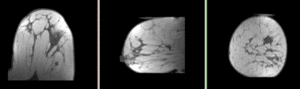

unregistered affine registered Bspline registered